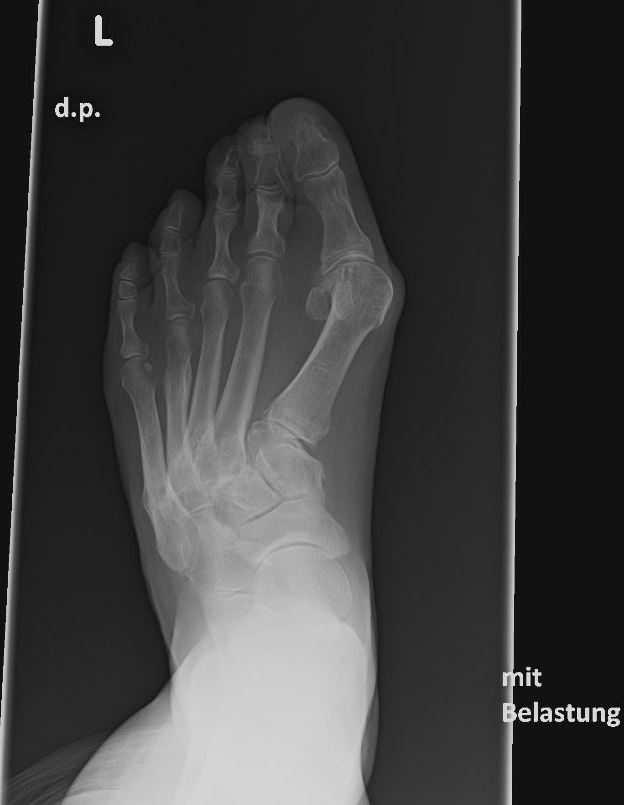

Häufig werden die Arthrosen der Lisfranc-Gelenklinie relativ spät diagnostiziert. Die Gründe dafür liegen oft daran, dass die Patienten selbst einen Schmerz an der Fußwurzel nicht mit dem Symptomkomplex Spreizfuß und Hallux valgus in Verbindung bringen. Auch werden in der Primärdiagnostik häufig nur vom Vorfuß Röntgenbilder angefertigt oder die angewandte Röntgentechnik erlaubt keine Einsicht in die Lisfranc-Gelenklinie.

Eine Röntgenaufnahme unter Belastung mit Abbildungen des ganzen Fußes a. p. (mit 15-20° Röhrenkippung) und seitlich, sowie Schrägaufnahmen, reichen meist zur Diagnose. Manchmal ist ein MRT und DVT ergänzend hilfreich. Selten wird die Indikation für ein SPECT CT gestellt (Abb. 6).

• konventionelle Röntgenbilder mit Belastung im Stehen a. p. und seitlich, ggf. schräg (Abb. 9, 10 und 11).